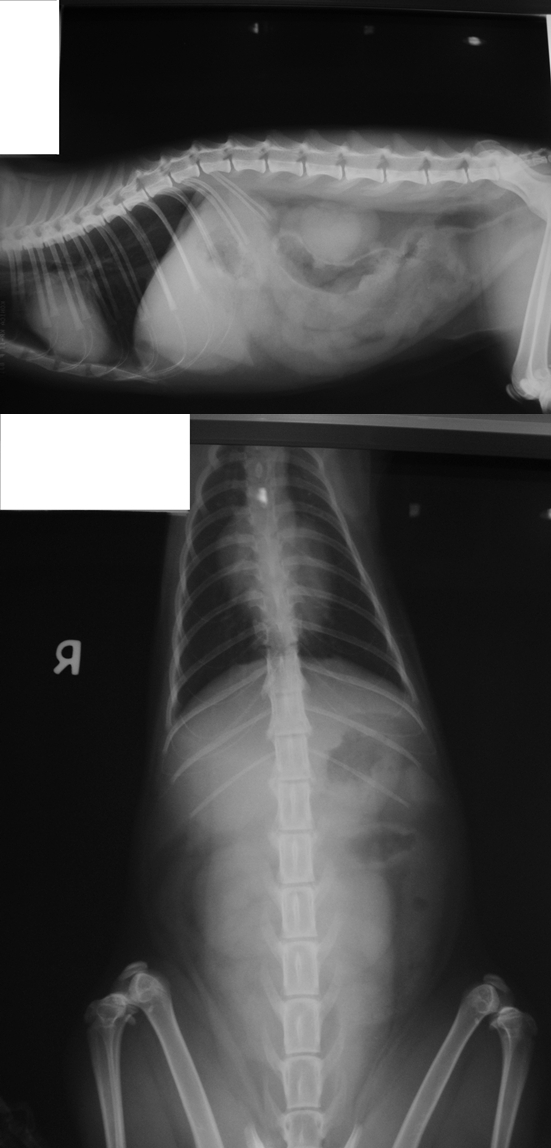

主題: 明道路 路倒嘴有血的黑貓 申請者姓名: 劉雅雲 花色: 申請日期: 2013-04-17 22:15:17 申請者部落格: 申請者臉書網址: 所在縣市/合作醫院: 高雄市/樂生動物醫院 治療費用: 10800元 需求人數: 23人 已結案 (2013-09-03 16:23:17) 報名人員: Jessie Chen x3(已付款)、董珈瑄(已付款)、周妍鈞(已付款)、Tin H(已付款)、楊閔華(已付款)、何偉靖(已付款)、郭小翼、謝佩芳(已付款)、Amy Li(已付款)、Rebecta Su、林廷軒(已付款)、馬豆漿 x2(已付款)、acctgbaby(已付款)、Anq Liao x2(已付款)、Angel Chou(已付款)、Marlie Sinma、Marlie Sinma、Eva Lee(已付款)、Alison Lee(已付款)、Lynn Lin(已付款)、MiniMe Chen(已付款)、Ya Shin Yang、Ya Shin Yang(已付款)、惠惠(已付款)、 候補人員: 動物病情說明: 3/21的中午在明正國小餵食區剛下車要放飼料就看到旁邊明道路上有一隻黑貓在路旁轉圈圈, 以為他在追昆蟲, 越看越奇怪他偏到路邊就趴下了. 過去看發現他嘴角有血應該是被車撞了, 貓躺在地方不太能移動, 趕快用洗衣網把他裝起來, 然後帶到醫院就醫, 發現此貓咪有剪耳, 是我在1月份結過紮原放的浪貓, 還好我在旁餵食剛好看到. 貓咪就醫有腦震盪的現象不吃, 走路會不平衡, 醫生有幫她打點滴, 照x光和血檢並做治療, 現在貓咪已經康復回到她熟悉的地方, 現在每天餵食時會在她那邊的小草地也放一碗飼料.

明細如下:

1.血液生化及電解質 1500

2.X 光片 (胸腔及腹腔各2張) 300*4=1200

3.住院 300*20=6000 <3/21 - 4/9>

4.點滴 300*7=2100

Total: 10800